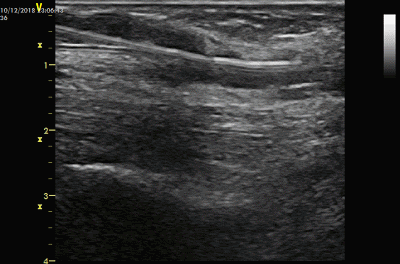

经过溶栓,有的AVG血流恢复较好,有的则恢复较弱血流,也有的血流仍然未恢复。

但即使未恢复,溶栓造成的以上变化也是有助于下一步的球囊碎栓治疗。

另外,血栓中“通道”的出现不仅可以使得血流初步恢复,而且在接下来的球囊扩张时可以成为一个“泄压”通道,即在球囊扩张时对两侧血栓的挤压产生的占位效应和压力可以通过该通道减轻,减少两侧血栓的移位,这一点在动脉吻合口尤为重要,减少血栓脱落进入动脉远端的风险。